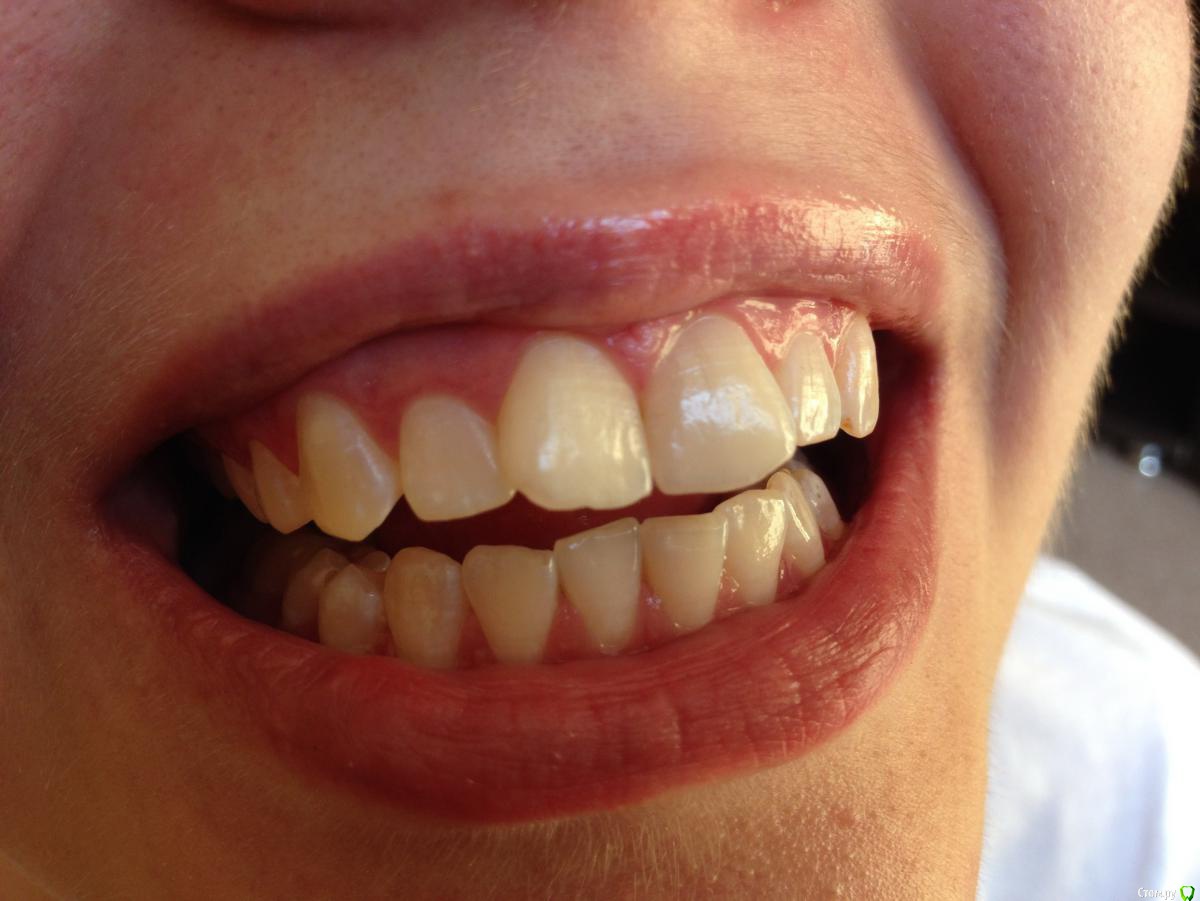

Ситуация следующая: сколько себя помню, всегда на зубах были белые пятна. Сейчас белые пятна почти на всех зубах и местами коричневые. Я не помню, когда появились коричневые пятна и очень беспокоюсь, что состояние эмали может в дальнейшем ухудшиться.

Врачи, у которых я консультировалась ставят разные диагнозы: флюороз, гипоплазия эмали. Рекомендуют наблюдаться и, к сожалению, не могут дать никаких прогнозов о развитии заболевания.

Фото зубов и снимок прилагаю. Буду очень благодарна за ваше профессиональное мнение.

Это у вас гипоплазия эмали вследствии флюороза, или так называемые крапчатые зубы. Что делать?, Ничего страшног просто участки с поврежденной эмалью очень хрупкие и поэтому выкрашиваются, просто пломбируйте, зато у вас устойчивостьт к кариесу повышенная